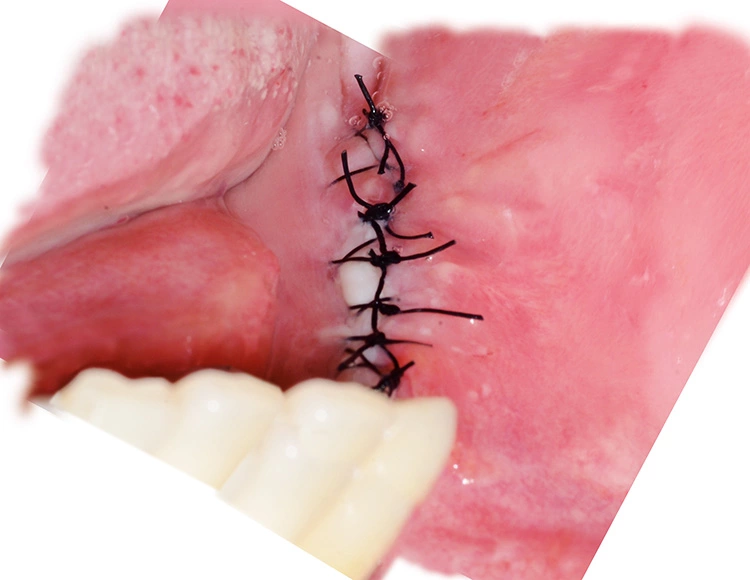

Implantation: 7 Monate nach Augmentation

Trotz der schlechten, hart- und weichgewebigen Grundvoraussetzungen konnte der Kieferkamm zufriedenstellend rekonstruiert werden. Die Augmentation des kombinierten, horizontalen und vertikalen Defekts mit Yxoss CBR®, Geistlich Bio-Oss®, Geistlich Bio-Gide®, autologem Knochen und PRF ermöglichte die Implantation mit hoher Primärstabilität in den rekonstruierten Bereich.